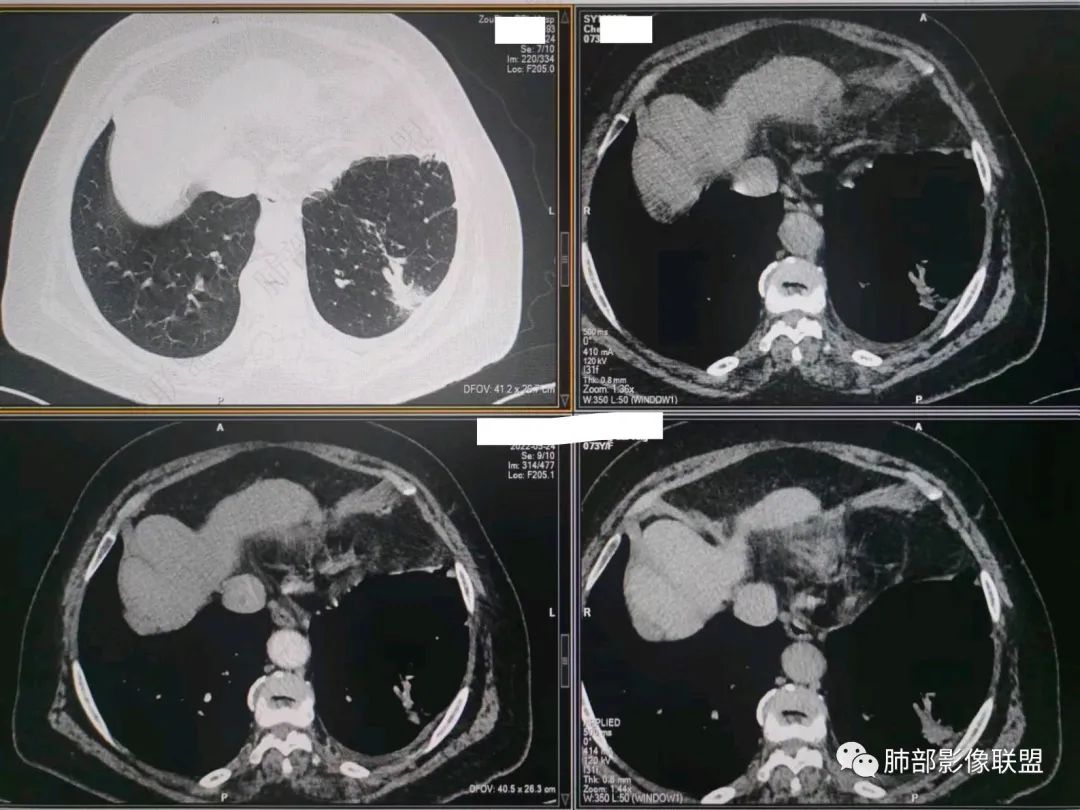

南边:今天的病例肺内部分基本都是炎性特点,问题就在于胸膜。

糊墙:肺内病灶不侵犯壁层胸膜或以外,与壁层胸膜相对而言分界清楚。

栽赃:病灶侵入壁层胸膜及胸膜外脂肪间隙、胸壁其他结构等,相对在病灶中央区域,与胸膜分界不清。

南边:看肺内病灶与胸膜分界清,增强后强化不一致,需要综合分析。

这是糊墙。

这就栽赃。都突到外面去了。

看看这个,骨头都侵袭了。

今天的病例有些伪影。

看起来就觉得放射状伪影。

我就不知道这些是胸水,伪影导致密度增高?还是胸膜增厚?

我只是邓较瘦:今天平扫的像栽赃, 增强感觉是增厚的胸膜。

南边:一般这类侵袭,是中央地带毛刷状延伸到胸膜内。

而且旁边这么宽的少,所以觉得很奇怪,不太符合,我是怀疑与照片有关。

你对比一下两侧的密度。肌肉密度不一样。

我只是邓较瘦:南大这个我感觉局部似乎是栽赃呢 箭头那里是啥?

南边:栽赃是这样过去的,中间不会脂肪间隙清晰。

胸壁的组织,除非你怀疑胸壁转移结节。

转移淋巴结。

局部侵犯。有差异。

我只是邓较瘦:这个是侵犯出去不是淋巴结吧?

南边:不是,你看看强化与淋巴结不一致。

我只是邓较瘦:强化与肿瘤差不多。

南边:是。